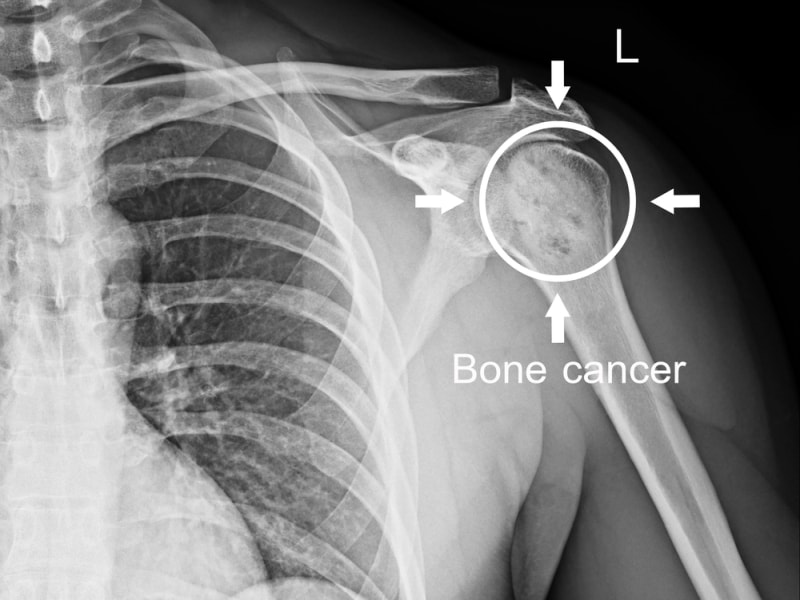

बोन कैंसर या हड्डी का कैंसर तब होता है, जब हड्डियों या उसके आस-पास की संरचनाओं में कोशिकाएँ अनियंत्रित रूप से विभाजित होकर ट्यूमर का निर्माण करती हैं। हालाँकि, बोन कैंसर के लक्षण किसी भी उम्र के व्यक्ति में प्रकट हो सकता है, लेकिन बच्चों और युवा वयस्कों में पाया जाना आम है। बोन कैंसर सामान्यतः दो प्रकार के होते हैं: प्राइमरी बोन कैंसर(जो हड्डियों के ऊतकों में विकसित होता है) और सेकेंडरी बोन कैंसर(वह कैंसर जो शरीर के किसी अन्य अंगों में विकसित होकर हड्डियों तक फैल जाए)। यदि प्राइमरी बोन कैंसर के टाइप्स की चर्चा करें, तो ओस्टियोसार्कोमा, कोंड्रोसार्कोमा और इविंग सार्कोमा इसके प्रकार हैं।

बोन कैंसर की उपस्थिति की जाँच करने के लिए और एक बेहतर उपचार योजना तैयार करने के लिए बोन कैंसर का निदान आवश्यक है। सर्वप्रथम बोन कैंसर के निदान के लिए, डॉक्टर कुछ शारीरिक परीक्षण कर सकता है, और मरीज़ से उसके पुराने चिकित्सा इतिहास यानी पुरानी बीमारी या पुरानी स्वास्थ्य संबंधी समस्या और पारिवारिक इतिहास के बारे में पूछ सकता है। इसके अतिरिक्त, बोन कैंसर के लक्षण की जाँच करने के लिए हड्डियों की इमेजेस देखने के लिए एक्स-रे का उपयोग किया जा सकता है, ट्यूमर और आस-पास की संरचनाओं की जाँच करने के लिए एमआरआई स्कैन और सीटी स्कैन की मदद से डिटेल्ड इमेजेस प्राप्त किए जा सकते हैं, हड्डी स्कैन में, कम खुराक वाले रेडियोएक्टिव मैटेरियल का इंजेक्शन नसों में दिया जाता है, और हड्डी की स्थिति का पता एक विशेष कैमरे द्वारा लगाया जाता है। इसके अतिरिक्त निदान का निश्चित परिणाम प्राप्त करने के लिए बायोप्सी की जा सकती है, जिसमें अफ़ेक्टेड एरिया से टिश्यू का एक छोटा सैंपल निकालकर माइक्रोस्कोप के द्वारा उसका परीक्षण किया जाता है।